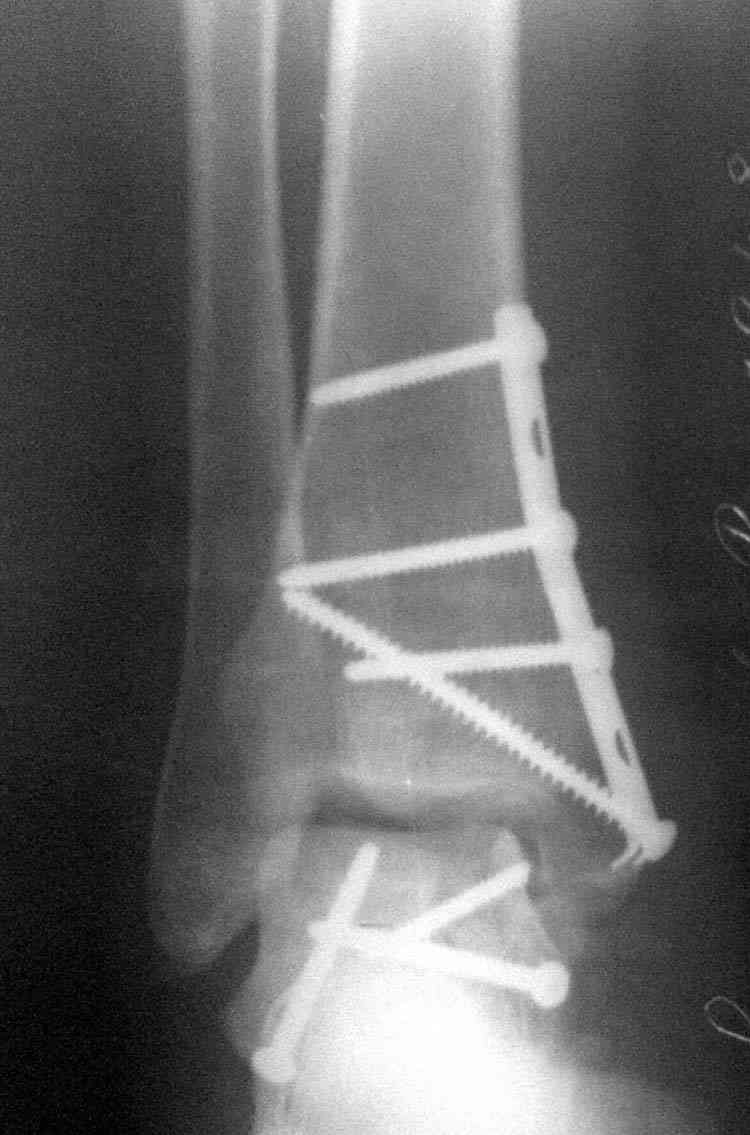

Случай с множественным оскольчатым переломом тарана оперированный из двойного доступа.

Через 8 мес.: